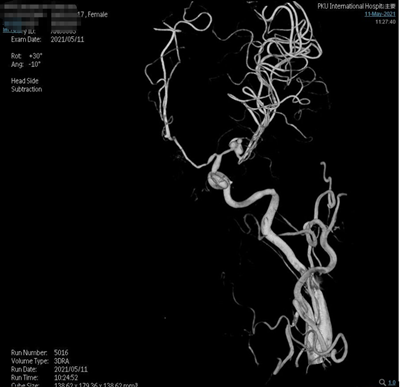

术前影像

脑动脉造影(外院,2021-5-10):双侧大脑中动脉分叉多发动脉瘤。

夹闭前造影